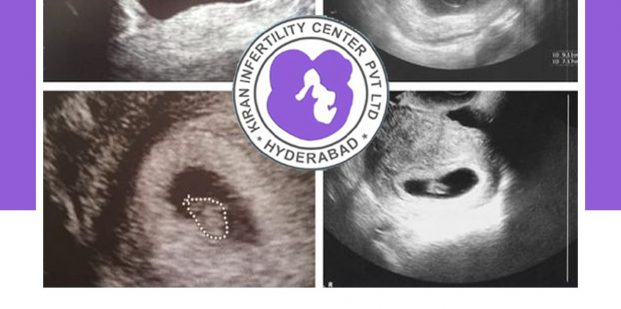

When you do take the home pregnancy test, it doesn’t quite seem real. But when you see the baby and the heartbeat, on the ultrasound it’s so incredible.

Ultrasound is an imaging technology that uses sound waves to create images. These images are displayed on the screen and you are able to see those. These scans are painless and there is no harm to you and your baby.

Pregnancy ultrasounds provide your doctor with plenty of valuable information. Early in pregnancy, ultrasounds are used to confirm the fetal heartbeat, location of your pregnancy and whether you’re carrying multiples.

Later allow the Doctor to monitor your baby’s growth, detect abnormalities, and see the position of your placenta. Toward the end of pregnancy, ultrasounds can be useful for checking the length of your cervix, if there is any suspicion that you may be in preterm labor, as well as to verify that your baby is in a heads-down position before labor.

6 weeks: This scan is used to confirm your estimated due date, check fetal heartbeat, number of fetuses and also to make sure the pregnancy is in uterus.